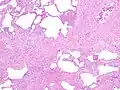

The histologic hallmarks of UIP, as seen in lung tissue under a microscope by a pathologist, are interstitial fibrosis in a "patchwork pattern", honeycomb change and fibroblast foci (see images below).[6][7]

Appearance of usual interstitial pneumonia (UIP) in a surgical lung biopsy at low magnification. The tissue is stained with hematoxylin (purple dye) and eosin (pink dye) to make it visible. The pink areas in this picture represent lung fibrosis (collagen stains pink). Note the "patchwork" (quilt-like) pattern of the fibrosis. -

Appearance of honeycomb change in a surgical lung biopsy at low magnification. The dilated spaces seen here are filled with mucin. Hematoxylin-eosin stain, low magnification. -